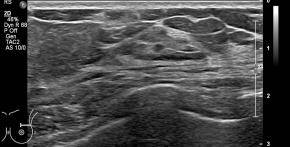

[355,Breast] 61/F,A palpable mass in the left breast

Breast

US,Etc,

What is your diagnosis?